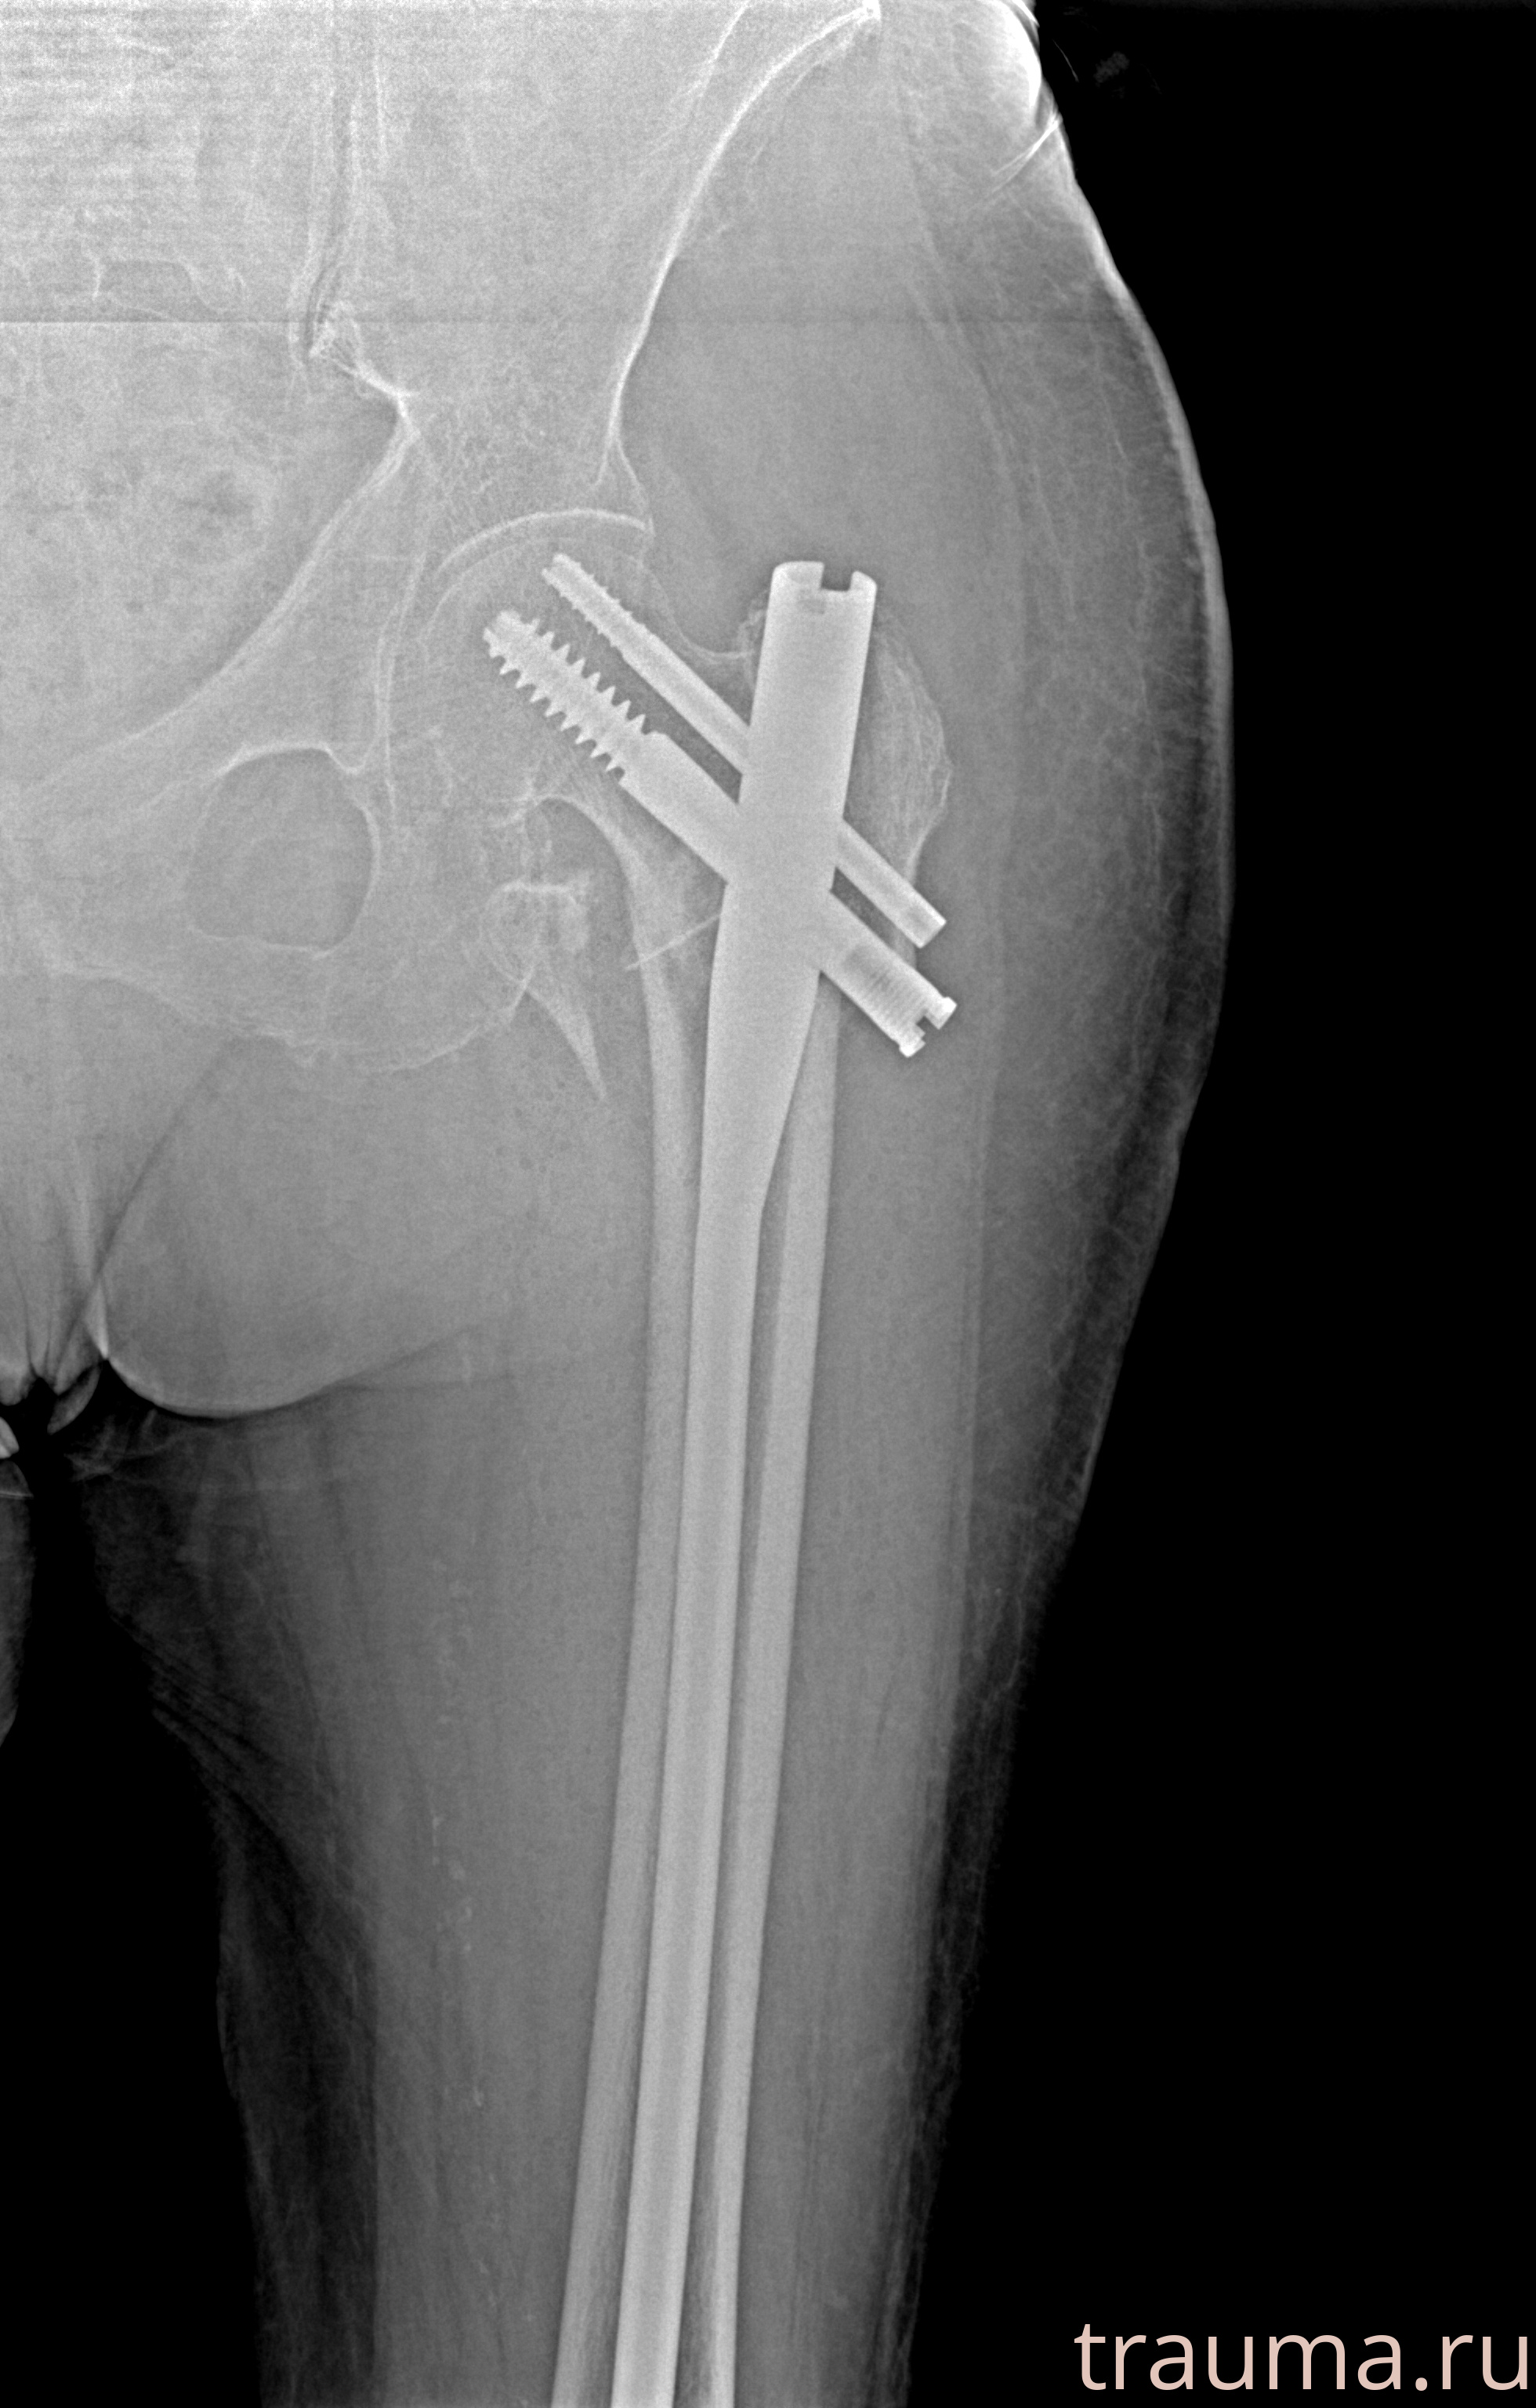

Рентгенограммы

Рентген на дому: по вашему адресу приезжает врач-рентгенолог, травматолог-ортопед с мобильным рентгеновским аппаратом, проводит диагностику травмы или заболевания, делает необходимые рентгенограммы, дает рекомендации по дальнейшему лечению. Получить качественные снимки в домашних условиях возможно благодаря уникальной методике, разработанной МосРентген Центром для института  Склифосовского